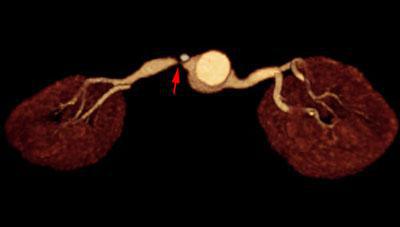

Estenosis intensa de arteria renal 2